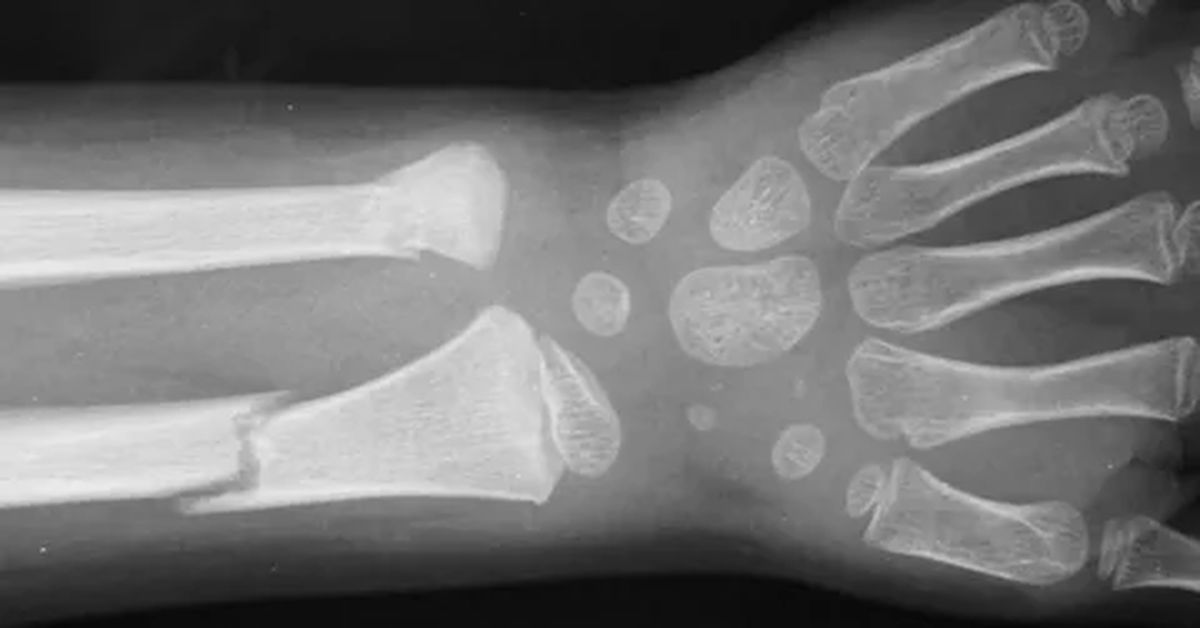

Hastalığın belirtileri arasında tekrarlayan kemik kırıkları, boy kısalığı, eğri kemikler ve bazen diş sorunları yer alır. Özellikle çocukluk ve ergenlik döneminde bu belirtiler daha belirgin hale gelir. Aileler, sık kırık yaşayan çocuklarda dikkatli olmalı ve düzenli kontrolleri aksatmamalıdır.

Kemik kırıkları sıklaşıyor, deformiteler artıyor veya hareket kısıtlılığı başlıyorsa cam kemik hastalığı tedavisi uygulanır. Tedavi, kemik yoğunluğunu artırmayı ve kırıkları önlemeyi amaçlar. İlaç tedavisi, fizik tedavi ve gerekirse cerrahi yöntemler tedavi planının temel unsurlarıdır. Hastanın yaşı, kırık geçmişi ve genel sağlık durumu dikkate alınarak kişiye özel bir plan hazırlanır.